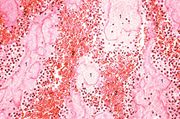

| 16:36, 19 August 2013 | IPLab4Thrombosis4.jpg (file) | 65 KB | Seung Park | This is another high-power photomicrograph of the ruptured fibrous cap (arrows) with hemorrhage (1) into the atherosclerotic plaque. Note the presence of cholesterol crystals. | 1 | |